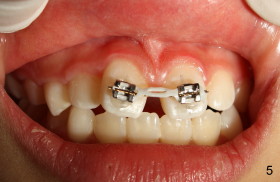

Eight-year-two-month girl has diastema between the maxillary central incisors.  It appears that the upper labial frenum (Fig.3 arrowheads, mirror view) bisects the interdental papilla (Fig.5).  Frenectomy is planned before orthodontic closure of the diastema.  Fig.4 is pre-op X-ray. Five months later, the diastema is closed.  The frenum appears to recede upward (Fig.6).  The bisected papilla seems to fuse (Fig.6,7).  Although the diastema has tendency to relapse when power chains are not used, fixed lingual retainer is planned to prevent the relapse when brackets are to be removed.  It appears that frenectomy is not so highly necessary for this purpose.

I evaluated the pics and I would only do a frenectomy if when you pull upward/outward on the lip, you see the marginal tissue blanching.  I have not heard of a doing a frenectomy to lengthen the upper lip.  I like the idea of a fixed retainer with her being 8 y.o.  This way she will not require a removable retainer in the mixed dentition.  You have shown me something I have never seen documented, the frenum moving superiorly as you close pace orthodontically!  Wow.  Good job.